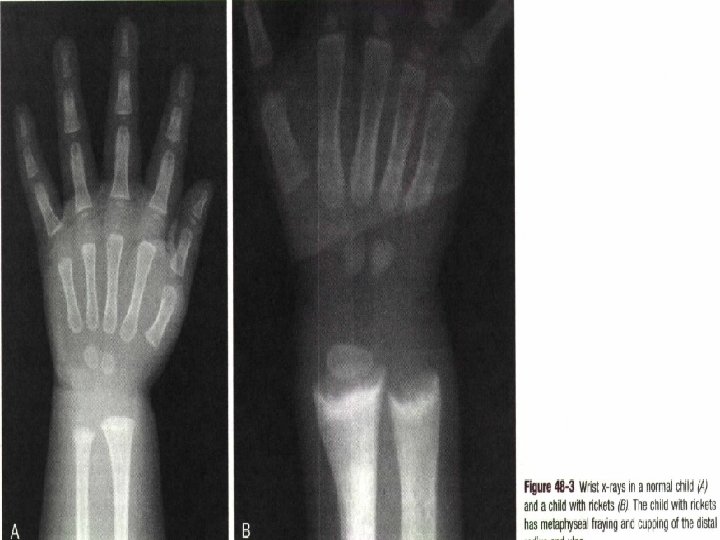

RICKETS • Rickets is defined as decreased or defective bone mineralization in growing children; osteomalacia is the same condition in adults. • The proportion of osteoid (the organic portion of bone) is excessive. • As a result, the bone becomes soft and the metaphyses of the long bones widen.

Clinical manifestations • Most manifestations of rickets are due to skeletal changes. • Craniotabes • Rachitic rosary • Growth plate widening is also responsible for the enlargement at the wrists and ankles. • Harrison groove

• Very low birth weight infants have an increased incidence of rickets of prematurity. • In older infants, poor linear growth, bowing of the legs on weight bearing (which can be painful), thickening at the wrists and knees, and prominence of the costochondral junctions (rachitic rosary) of the rib cage occur. • At this stage, x-ray findings are diagnostic.